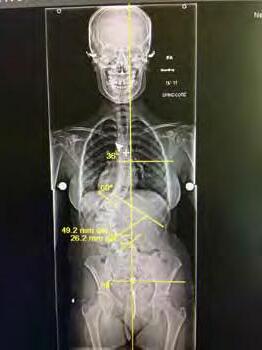

TOP 1% OR HIGHER ON NATIONAL EXAMS INCLUDING MOST RECENT BOARD RE-CERTIFICATION 30+ YEARS OF SPINE SURGERY EXPERIENCE DOUBLE BOARD-CERTIFIED 20+ YEARS AMERICAN BOARD ORTHOPEDIC SURGERY AMERICAN BOARD SPINE SURGERY PATRICK MCNULTY, MD F.A.B.O.S. • F.A.B.S.S. JOHNS HOPKINS FELLOWSHIP IN SPINE SURGERY 2 OFFICE LOCATIONS: 3012 South Durango Drive • Las Vegas, NV 89117 3175 Saint Rose Parkway, Ste 320 • Henderson, NV 89052 702-463-1424 • www.mcnultyspine.com • mcnultyteam@mcnultyspine.com LOWER BACK PAIN • NECK PAIN • SCIATICA • SCOLIOSIS• SPINAL STENOSIS SPINAL INJECTIONS • MINIMALLY INVASIVE SURGERY • KYPHOSIS • SPINAL RECONSTRUCTION MEDICOLEGAL EVALUATION/TREATMENT/EXAMINATIONS 27